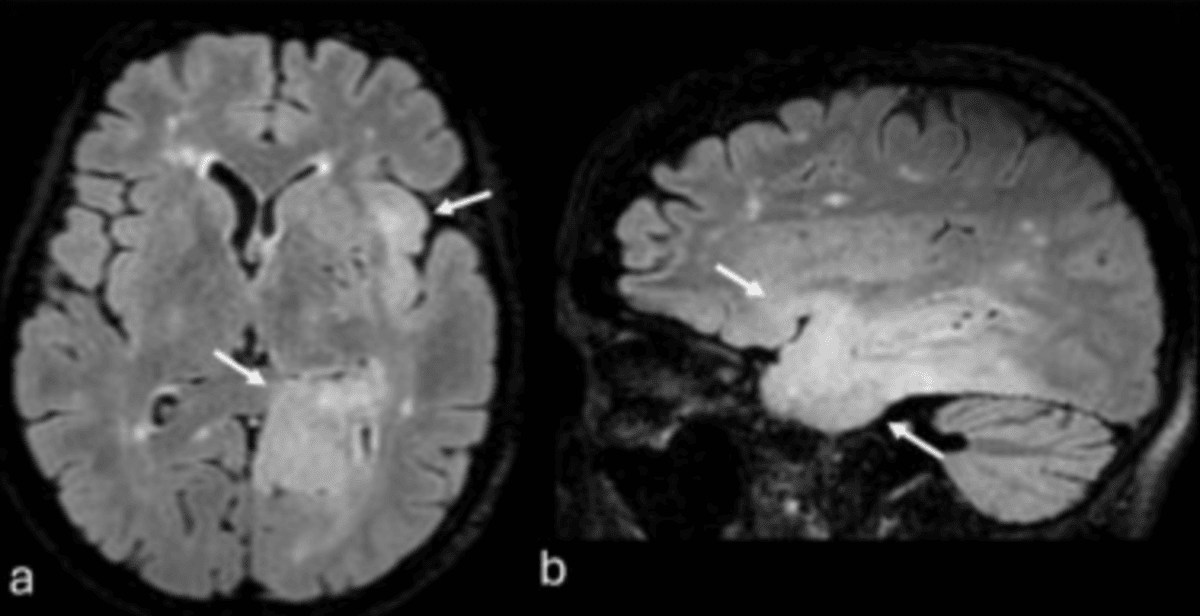

How Modern Imaging Supports Early Detection

MRI and multi-organ scanning

Magnetic Resonance Imaging (MRI) uses magnets and radio waves to make extremely high-resolution, 3D images. The detail provided by these scans allows for the earliest signs of cancer to be spotted across multiple organs, even before symptoms appear.

Early detection using advanced imaging techniques is a powerful tool for improving patient outcomes. The information from MRI scans can help monitor disease progression, assist doctors in determining the course of treatment, and track how effective treatments are.

Image adapted from Fig. 1 and used under the Creative Commons license.